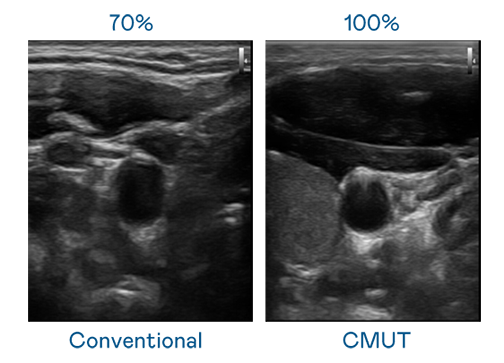

CMUT 技術是一種用電容式微機電元件來產生超音波訊號的技術。與傳統 PZT 壓電式技術相比,CMUT 頻寬增加 30%,更寬頻的超音波訊號讓影像解析度大幅提升,是實現高影像品質醫療超音波掃描、促進精準醫療發展的關鍵技術。

超音波影像的解析度高低,首先取決於探頭能發出的訊號頻寬。713贵宾会 CMUT 可提供高清晰的超音波訊號,提供高頻寬、高靈敏度、影像紋理細節更高的超音波影像,協助醫護人員縮短影像判讀時間及利用精準的醫療影像進行診斷。